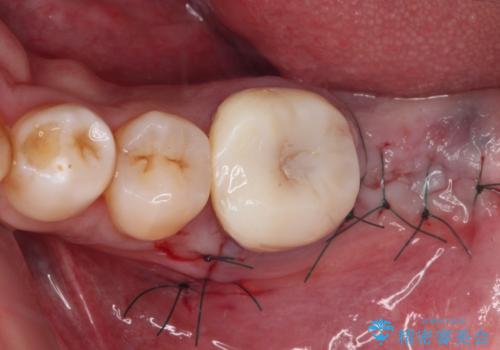

抜歯が必要な奥歯 ストローマン・インプラント補綴治療

- 近医にて奥歯の抜歯が必要と言われたとのことで来院された患者様です。

診査の結果、歯が破折しており、抜歯が必要な状態でした。

最後方歯であるため、入れ歯かインプラントかどちらかの補綴治療を行うこととなりますが、ご希望によりインプラント補綴治療を行うこととしました。

インプラントにはストローマン社のSLActiveを使用し、埋入から補綴までおよそ3か月と、短期間で治療を進めることができました。